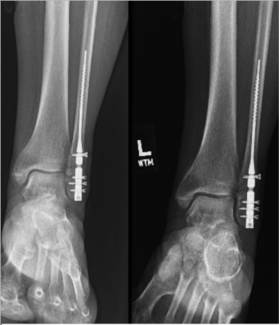

Alexa Bykowski, DPM; Ian Barron, DPM, FACFAS; Zachary Hill, DPM

Can intramedullary (IM) nails reduce and stabilize fibular fractures? These authors take a closer look at recent literature, present indications and contraindications, and compare plates with IM nails.